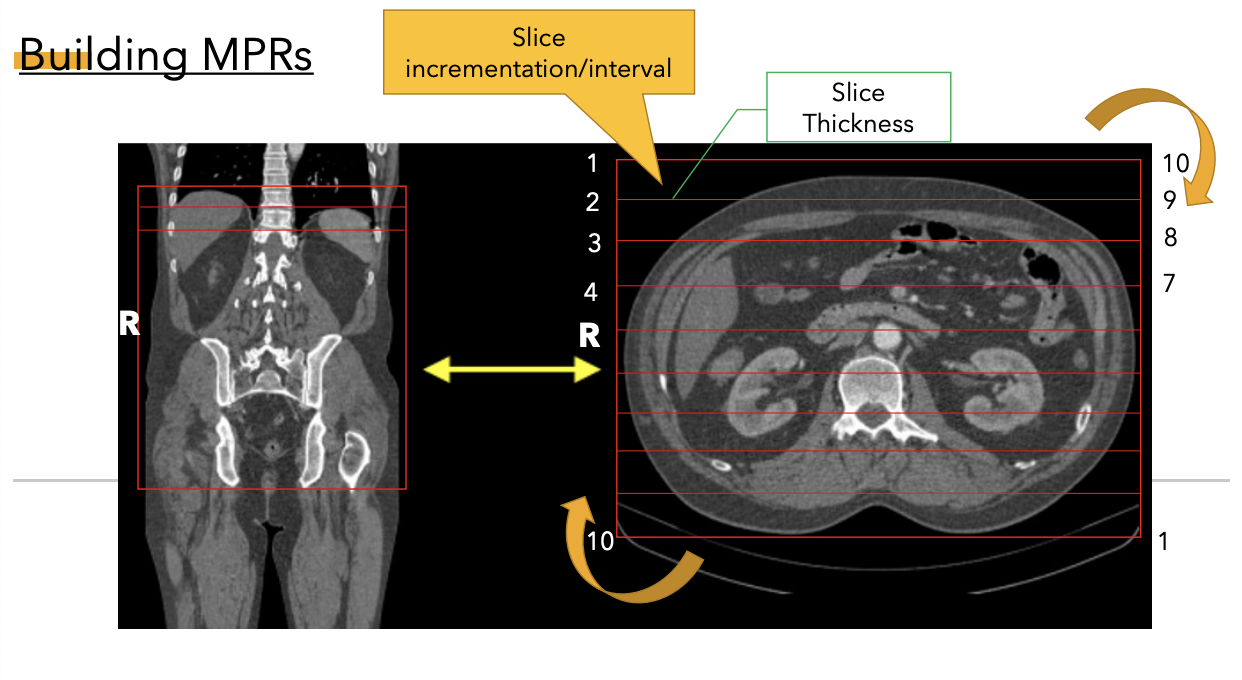

1

A

• manual MPRs requires operator to input the criteria such as thickness of MPR, the plane desired and the incrementation of resulting image

• scanner created MPR: automatically generated by the scanner software